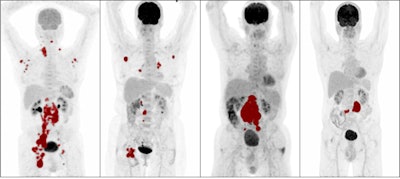

Maximum intensity projections of patients with high metabolic tumor volume (MTV), low MTV, high dissemination, and low dissemination. Tumor delineations are indicated in red. From left: high MTV and high dissemination, low MTV and high dissemination, high MTV and low dissemination, and low MTV and low dissemination. Image courtesy of the European Journal of Nuclear Medicine and Molecular Imaging.Current clinical scoring systems, such as the international prognostic index (IPI), fail to identify high-risk patients who need novel treatment approaches the most, according to the authors. In this study, the researchers aimed to evaluate the added value of baseline radiomics features in DLBCL patients compared with IPI scores.